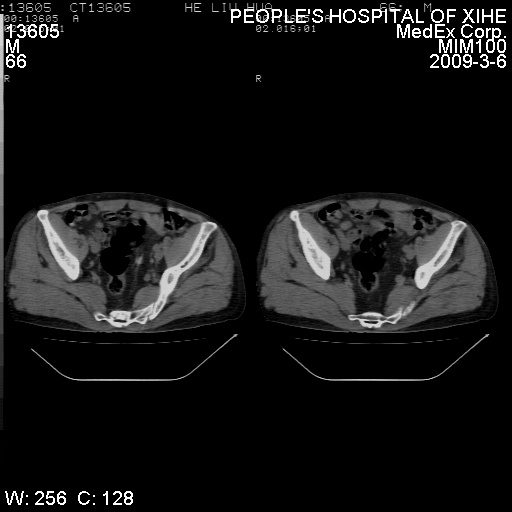

标题: CT18522:男,66岁。考虑结核有错吗 [打印本页]

标题: CT18522:男,66岁。考虑结核有错吗

x线片示:骶骨密度增高。

考虑----腰椎骶化-----退变-----椎管狭窄

腰骶椎退行性改变。

退行性变,椎体滑脱

腰椎滑脱并有退变

退行性变,椎体滑脱。建议同椎体平行进一步扫描。